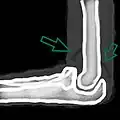

A traumatic right knee effusion. Note the swelling lateral to the kneecap as marked by the arrow.